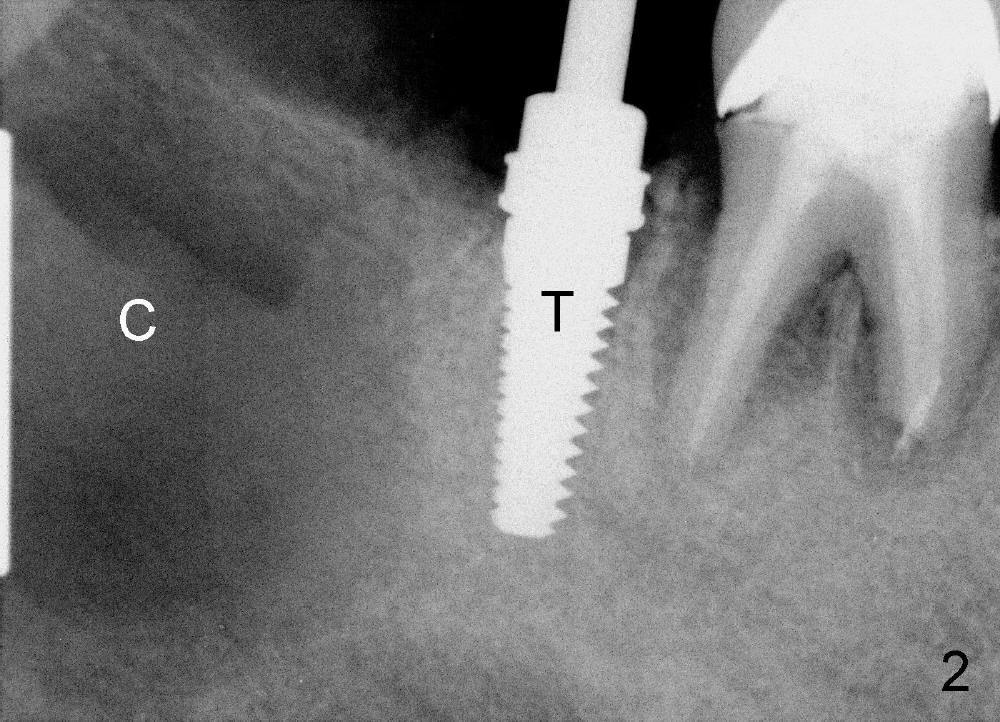

Immediately post extraction and cyst enucleation, osteotomy is formed in the mesial socket of the 2nd molar surrounded by intact bone (Fig.2 (T: 5x17 mm tap)).  Separation of the inferior alveolar neurovascular bundle from the cyst causes severe hemorrhage, which is stopped temporarily by gauze.